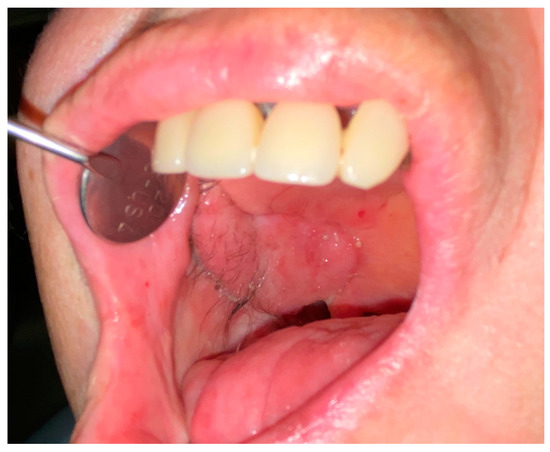

The average follow-up was nine months (range: 2–15 months). All of the reconstructions were successful and there were no major postoperative vascular complications. All flaps completely restored the oral cavity anatomy in terms of both tissue quality and quantity. No minor postoperative complications (e.g., partial flap loss caused by dehiscence/oroantral communication) were noted. Temporary paralysis of the frontal branch of the facial nerve was observed in one case. No postoperative functional issues at either the donor or recipient site were encountered; all patients healed well, as shown in Figure 9 and Figure 10.

Figure 9.

Reconstruction outcomes. Case 1. (A): The intraoral insert. (B): 2 weeks after surgery. (C): 3 months after surgery.